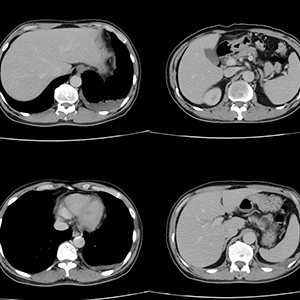

CT calcium scoring, also may be called a coronary calcium scan or heart scan, is a specialized X-ray scan used as a routine screening for early detection of calcium-containing plaque in the arteries. Calcium build up in the coronary arteries affects the level of blood and oxygen delivered to the heart, a key risk factor for heart disease. As calcium builds up in the arteries, they can begin to narrow or become blocked. The narrowing or blockage can result in symptoms such as chest pain, shortness of breath, and/or fatigue.

After your scan, one of our board-certified radiologists will evaluate the images and detail the amount of calcium plaque in each of your heart’s arteries. The results are scored numerically to indicate your risk level for heart disease.

• 0: No calcium deposits present, indicating a low risk

• 1 – 10: Minimal calcium deposits, suggesting a low to moderate risk

• 11 – 100: Moderate calcium deposits, indicating a moderate to high risk

• 101 – 400: High calcium deposits, indicating a high risk

• 400 and above: Extensive calcium deposits, indicating a severe risk

Your doctor will receive the full report of the results and analyze it alongside the rest of your medical history. Once reviewed, your doctor will follow-up to help you understand what the scores mean for your heart health and determine whether lifestyle changes, medication, or additional tests are recommended.